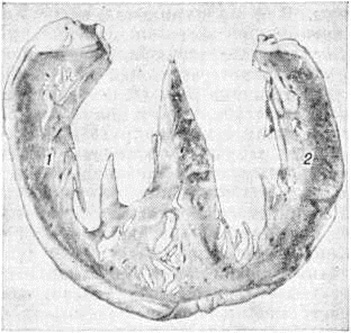

Патологическая анатомия. При Лёгочное сердце увеличивается объем сердца за счёт гипертрофии миокарда и расширения правых его полостей. В фазе компенсации хронический Лёгочное сердце отмечается концентрическая гипертрофия правого желудочка с тоногенным его расширением: полость желудочка равномерно увеличивается во всех направлениях, стенка утолщена (гипертрофия); мышца имеет розовый цвет и эластическую консистенцию. В стадии выраженной декомпенсации хронический Лёгочное сердце наблюдается эксцентрическая гипертрофия или миогенное расширение полости правого желудочка с истончением его стенки: расширение полости может быть неравномерным, сердце как бы расслаблено и растянуто кровью; мышца сердца становится дряблой, цвет её серо-розовый с глинистым оттенком. Между этими крайними двумя видами расширения полости сердца имеются переходные стадии, характеризующиеся различным соотношением между степенью гипертрофии и величиной расширения полости. При указанных изменениях стенок и полостей правых камер сердца заключение о Лёгочное сердце делается в тех случаях, если обнаруживается заболевание органов дыхания или сосудов лёгких, способное обусловить артериальную лёгочную гипертензию.

Степень гипертрофии миокарда правого желудочка определяют на вскрытии путём либо раздельного взвешивания сердца, либо измерения толщины стенки правого желудочка в области основания. В норме масса миокарда правого желудочка относится к массе левого приблизительно как 1 : 2 (желудочковый индекс). Изменение этого соотношения в сторону увеличения массы миокарда правого желудочка указывает на его гипертрофию, так же как и патологический утолщение его стенки (нормальная толщина стенки правого желудочка у основания колеблется примерно от 3,3 до 4,9 миллиметров). Однако, чтобы сделать окончательное заключение о том, что имеется гипертрофия миокарда правого желудочка, необходимо учесть все патологический изменения сердца у больного. Так, желудочковый индекс может не измениться, если наряду с гипертрофией миокарда правого желудочка имеется и гипертрофия левого (например, в связи с гипертонической болезнью). Толщина стенки правого желудочка может оставаться также «нормальной», если увеличение массы миокарда желудочка сопровождается выраженным расширением его полости и, значит, соответствующим истончением стенки.

При значительных степенях гипертрофии миокарда правого желудочка им может быть образована верхушка сердца, которую в норме формирует миокард левого желудочка. О степени гипертрофии и расширения правого желудочка свидетельствует удлинение его приносящего и выносящего трактов. Вначале происходит удлинение приносящего тракта (в норме его длина 72—81 миллиметров), а затем выносящего (в норме его длина 88—91 миллиметров).

Особенности гипертрофии миокарда правого желудочка в значительной мере зависят от характера нарушений внутрисердечной гемодинамики. Объёмные перегрузки правого желудочка ведут к преимущественной гипертрофии его трабекулярного аппарата, в то время как собственно стенка значительно не утолщается. Перегрузки давлением обусловливают преимущественно гипертрофию собственно стенки правого желудочка наряду с гипертрофией трабекул (рисунок 1). Соотношение трабекулярно-папиллярного аппарата и собственно стенки может в определённой степени отражать соотношение перегрузок объёмом и давлением, существовавших при жизни больного.